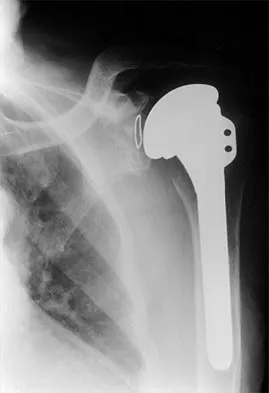

Question 2High Yield

A 70-year-old man who underwent an uncomplicated large rotator cuff repair 6 months ago is now seeking a second opinion regarding persistent pain and weakness in his shoulder. Examination reveals that his incision is well healed and unreactive. The surgical report suggests that the tendons were secured back to bone with sutures through the greater tuberosity. Figure 28 shows a radiograph that was obtained 1 week ago. What is the most likely diagnosis?

Explanation

Symptoms can persist following a rotator cuff repair for a variety of reasons. In the early postoperative period, infection is the primary concern. Stiffness and loss of motion can occur because of postoperative scarring. Complex regional pain syndrome can occur but is rare, and the diagnosis is not made with a plain radiograph. This radiograph shows a superiorly migrated humeral head that articulates with the acromion, indicating that the repair has failed. While large to massive tears may fail more commonly than once thought, the clinical outcome may be satisfactory in many patients. Mansat P, Cofield RH, Kersten TE, Rowland CM: Complications of rotator cuff repair. Orthop Clin North Am 1997;28:205-213.